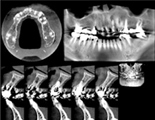

歯科用CTスキャンによるX線画像の撮影により、今までの平面X線写真では見ることができなかった骨の詳しい形や血管・神経の走行までわかるようになりました。

歯科用CTは今まで2次元だったレントゲンを3次元で表現することができます。

より詳しい骨の形、血管・神経の位置がわかります。